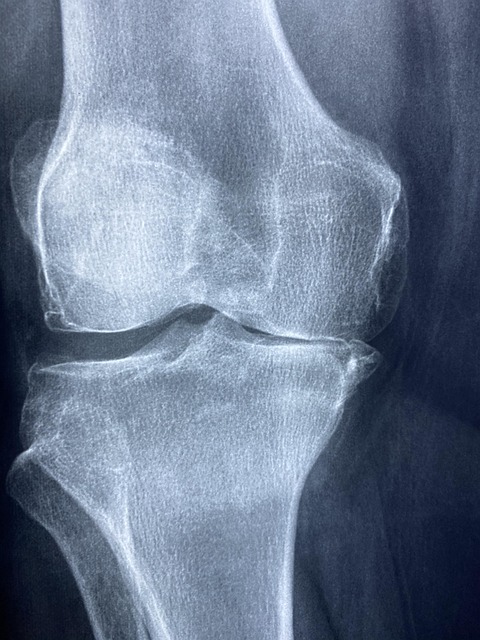

원인 11. 무릎의 퇴행성 관절염

무릎의 퇴행성관절염은 관절을 막아주는 연골이 점점 손상됐거나 역행하여 관절을 결성하는 뼈와 인대가 무너져 염증과 통증을 일으키는 질환으로 점점 늙을수록 가끔가다 잘 나쁘게 되는 것으로 알려져 있고요. 골관절염은 주로 무릎 관절에 발생하지만 어깨, 손가락, 고관절, 척추 등 각종 관절에서도 나타날 수 있고요.